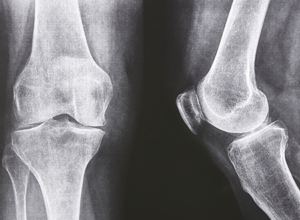

Regal Cutting Tools is proud to be part of the production of replacement joints that give people around the world the ability to regain their mobility.